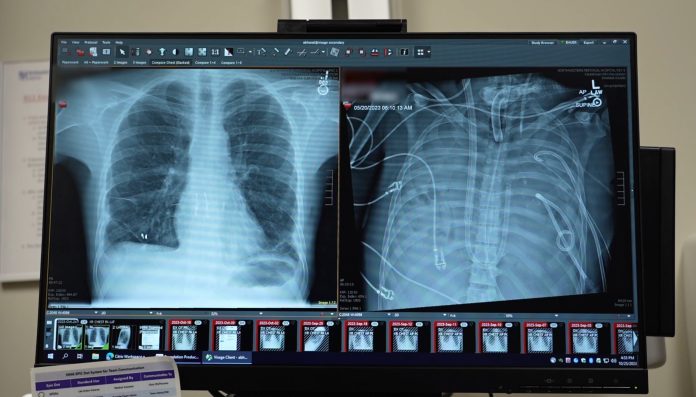

Bharat și colegii săi au dezvoltat un sistem de plămâni artificiali care a înlocuit complet funcția pulmonară prin eliminarea dioxidului de carbon și injectarea oxigenului în sânge, menținând un flux stabil. Acest lucru le-a permis să îndepărteze chirurgical plămânii infectați, stabilizând astfel tensiunea arterială a pacientului și menținând infecția sub control, permițând îmbunătățirea stării acestuia pentru a primi un transplant. Două zile mai târziu, plămânii donatori au devenit disponibili și transplantul a fost efectuat.

O analiză a plămânilor îndepărtați, folosind transcriptomica unicelulară și spațială, a relevat semne de deteriorare ireversibilă a țesuturilor în șapte regiuni pulmonare distincte, prezentând semnături moleculare ale bolii pulmonare fibrotice în stadiu terminal. Aceste rezultate au arătat că unii pacienți diagnosticați cu ARDS s-ar putea să nu se poată recupera pe cont propriu.